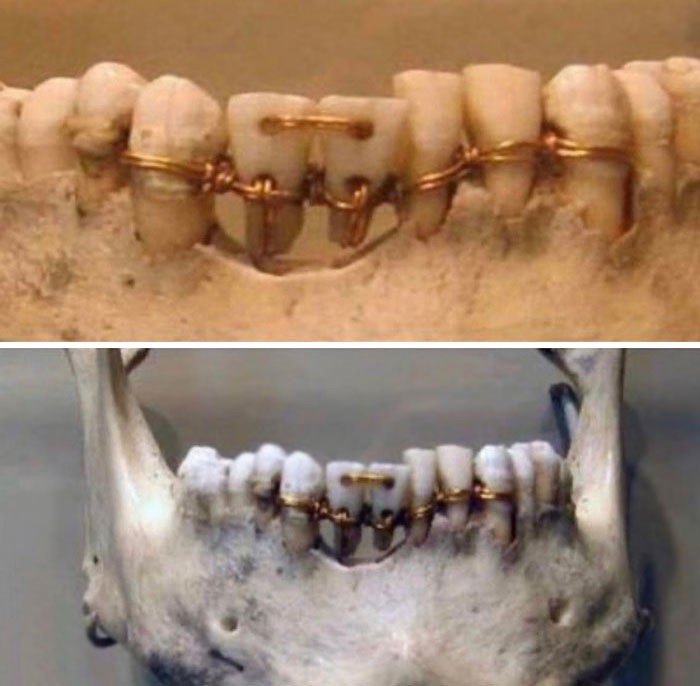

23. Стоматология в Древнем Египте